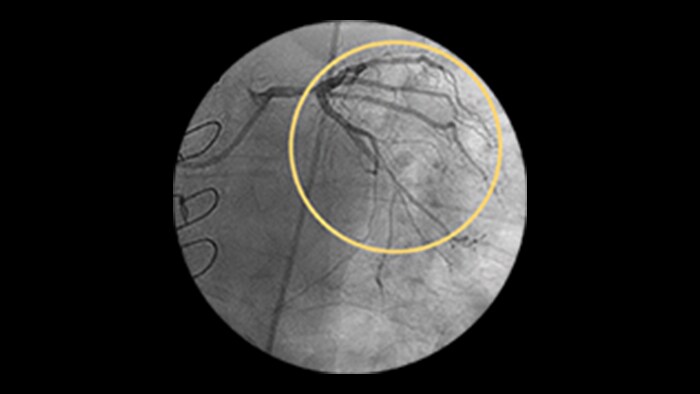

Saphenous vein graft and thrombus lesions

SVG patency rates have been reported at approximately 80% at 1 year and approximately 50% at 15 years and beyond.1